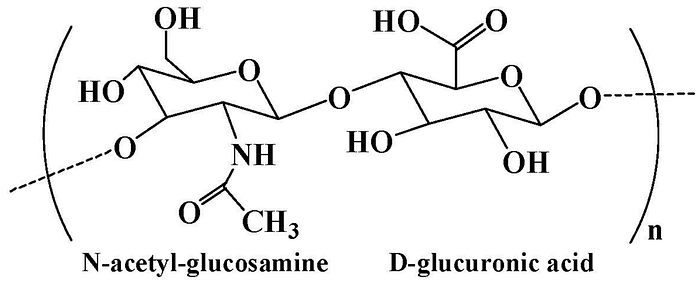

Hyaluronic acid is a natural polysaccharide found in the extracellular matrix prominently throughout the body. It is comprised of N-acetyl-glucosamine and D-glucuronic acid residues. The extracellular matrix (ECM) helps cells attach to, and communicate with, nearby cells, and plays an important role in cell growth, cell movement, and other cell functions. As a main component of the ECM, hyaluronic acid plays a significant role in lubrication, water absorption, and retention for tissue and the ECM, structural and space-filling functions, and interacts with various cell receptors to coordinate cell communication and behavior.

So why did we choose our nanogel to be made out of hyaluronic acid? We choose hyaluronic acid because it is well known for its bioactivity, which means that it can produce a certain therapeutic effect when interacting with biological systems. Hyaluronic acid also has other advantageous properties such as its nontoxicity, nonallergy, biocompatibility, and biodegradability.

The chemical modification of hyaluronic acid is mainly focused on three distinct functional groups: the glucuronic carboxylic acids, the primary and secondary hydroxyl groups, and the N-acetyl groups. Altering any of these functional groups can result in changes in the properties (mechanical or chemical) and biological activity of hyaluronic acid. This is important because we want our system to be customizable to fit the needs of a specific patient based on where the tumor is located or what specific drug we are using.

Hyaluronic acid contains hydroxyl and carboxyl functional groups in the main chain, which can be chemically modified to obtain hyaluronic acid derivatives with unique biological and physicochemical properties. The carboxyl group in hyaluronic acid can be changed to create derivatives. Ester derivatives can be made using alkyl halides, diazomethane, or tosylate activation and amide derivatives can be formed using carbodiimides or carbonyldiimidazole. Furthermore, hyaluronidase, an enzyme that breaks down hyaluronic acid, is found at higher levels in many cancer cells. Because of this, hyaluronic acid-based hydrogels, which can be broken down by the body, are often used to deliver local therapies. While I am talking about hydrogels here, it is important to note that these characteristics can still be applied to nanogels, which are just a smaller version of hydrogels.

- Hyaluronic acid has a high affinity to the CD44 receptor, which is commonly over-expressed in cancer cells. This means that hyaluronic acid helps the drug delivery system enter and affect the tumor cells more directly. Hyaluronic acid can bind to these CD44 receptors using six monosaccharide units — HA6.